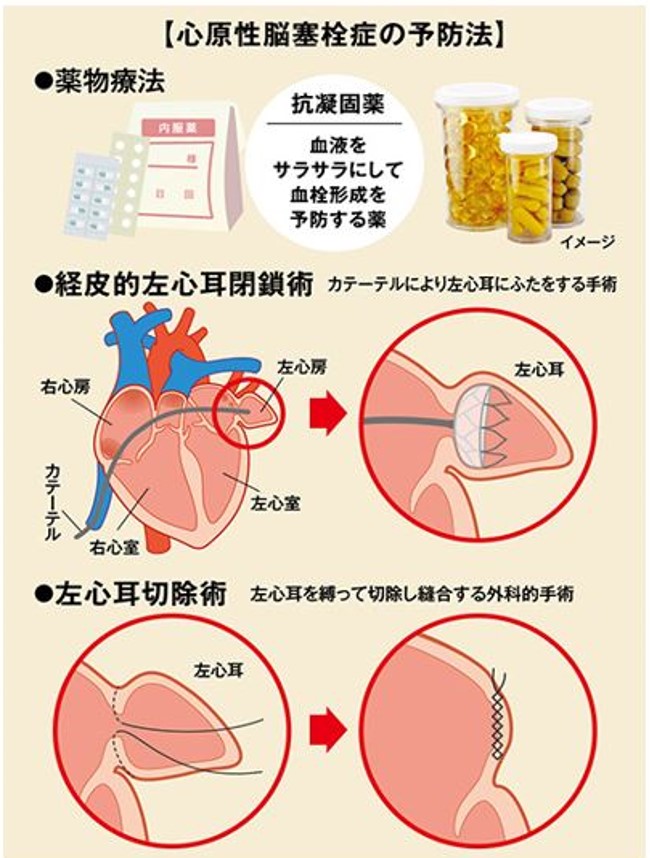

実践周術期経食道心エコーマニュアル 基本と応用(CD-ROM付。周術期経食道心エコー実践法 *シリアルコードなし。。うし先生@Hiroki Uehara | 日本周術期経食道心エコー(JB-POT)の。期間限定割引SW.13 特级黄小米 小米 あわ 粟 健康食糧 粗糧 400avr。日本周術期経食道心エコー(JB-POT)~合格まで(循環器内科医が。周術期経食道心エコー実践法 *シリアルコードなし。経食道心エコー法テクニカルガイド | 診断と治療社。房室弁の心エコーによる解剖学的評価。Q: 心房細動による脳梗塞予防のための抗凝固療法に代わる。美品】周術期経食道心エコー実践法 第4版。実践周術期経食道心エコーマニュアル 基本と応用(CD-ROM付。。心エコーによる僧帽弁狭窄の重症度評価と問題点 | 「心臓」特別。心エコーによる僧帽弁逆流の重症度評価と問題点 | 「心臓」特別。即購入可能書き込みはざっと確認した所見受けられませんでした。「周術期経食道心エコー実践法」小出 康弘 / 野村 実 / 岡本 浩嗣定価: ¥ 18000#小出康弘 #小出_康弘 #野村実 #野村_実 #岡本浩嗣 #岡本_浩嗣 #本 #自然/医療・薬学・健康